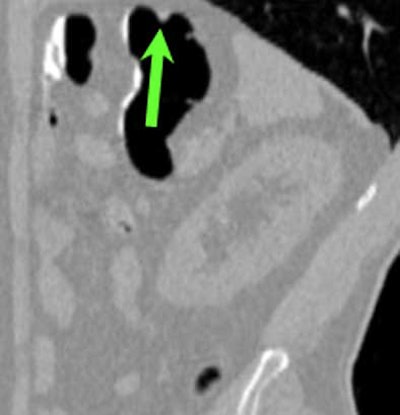

| Top to bottom: A 10-mm polyp in the splenic flexure can be seen in axial, sagittal, coronal, and 3D views. All images courtesy of Dr. Riccardo Iannaccone, University of Rome "La Sapienza." |